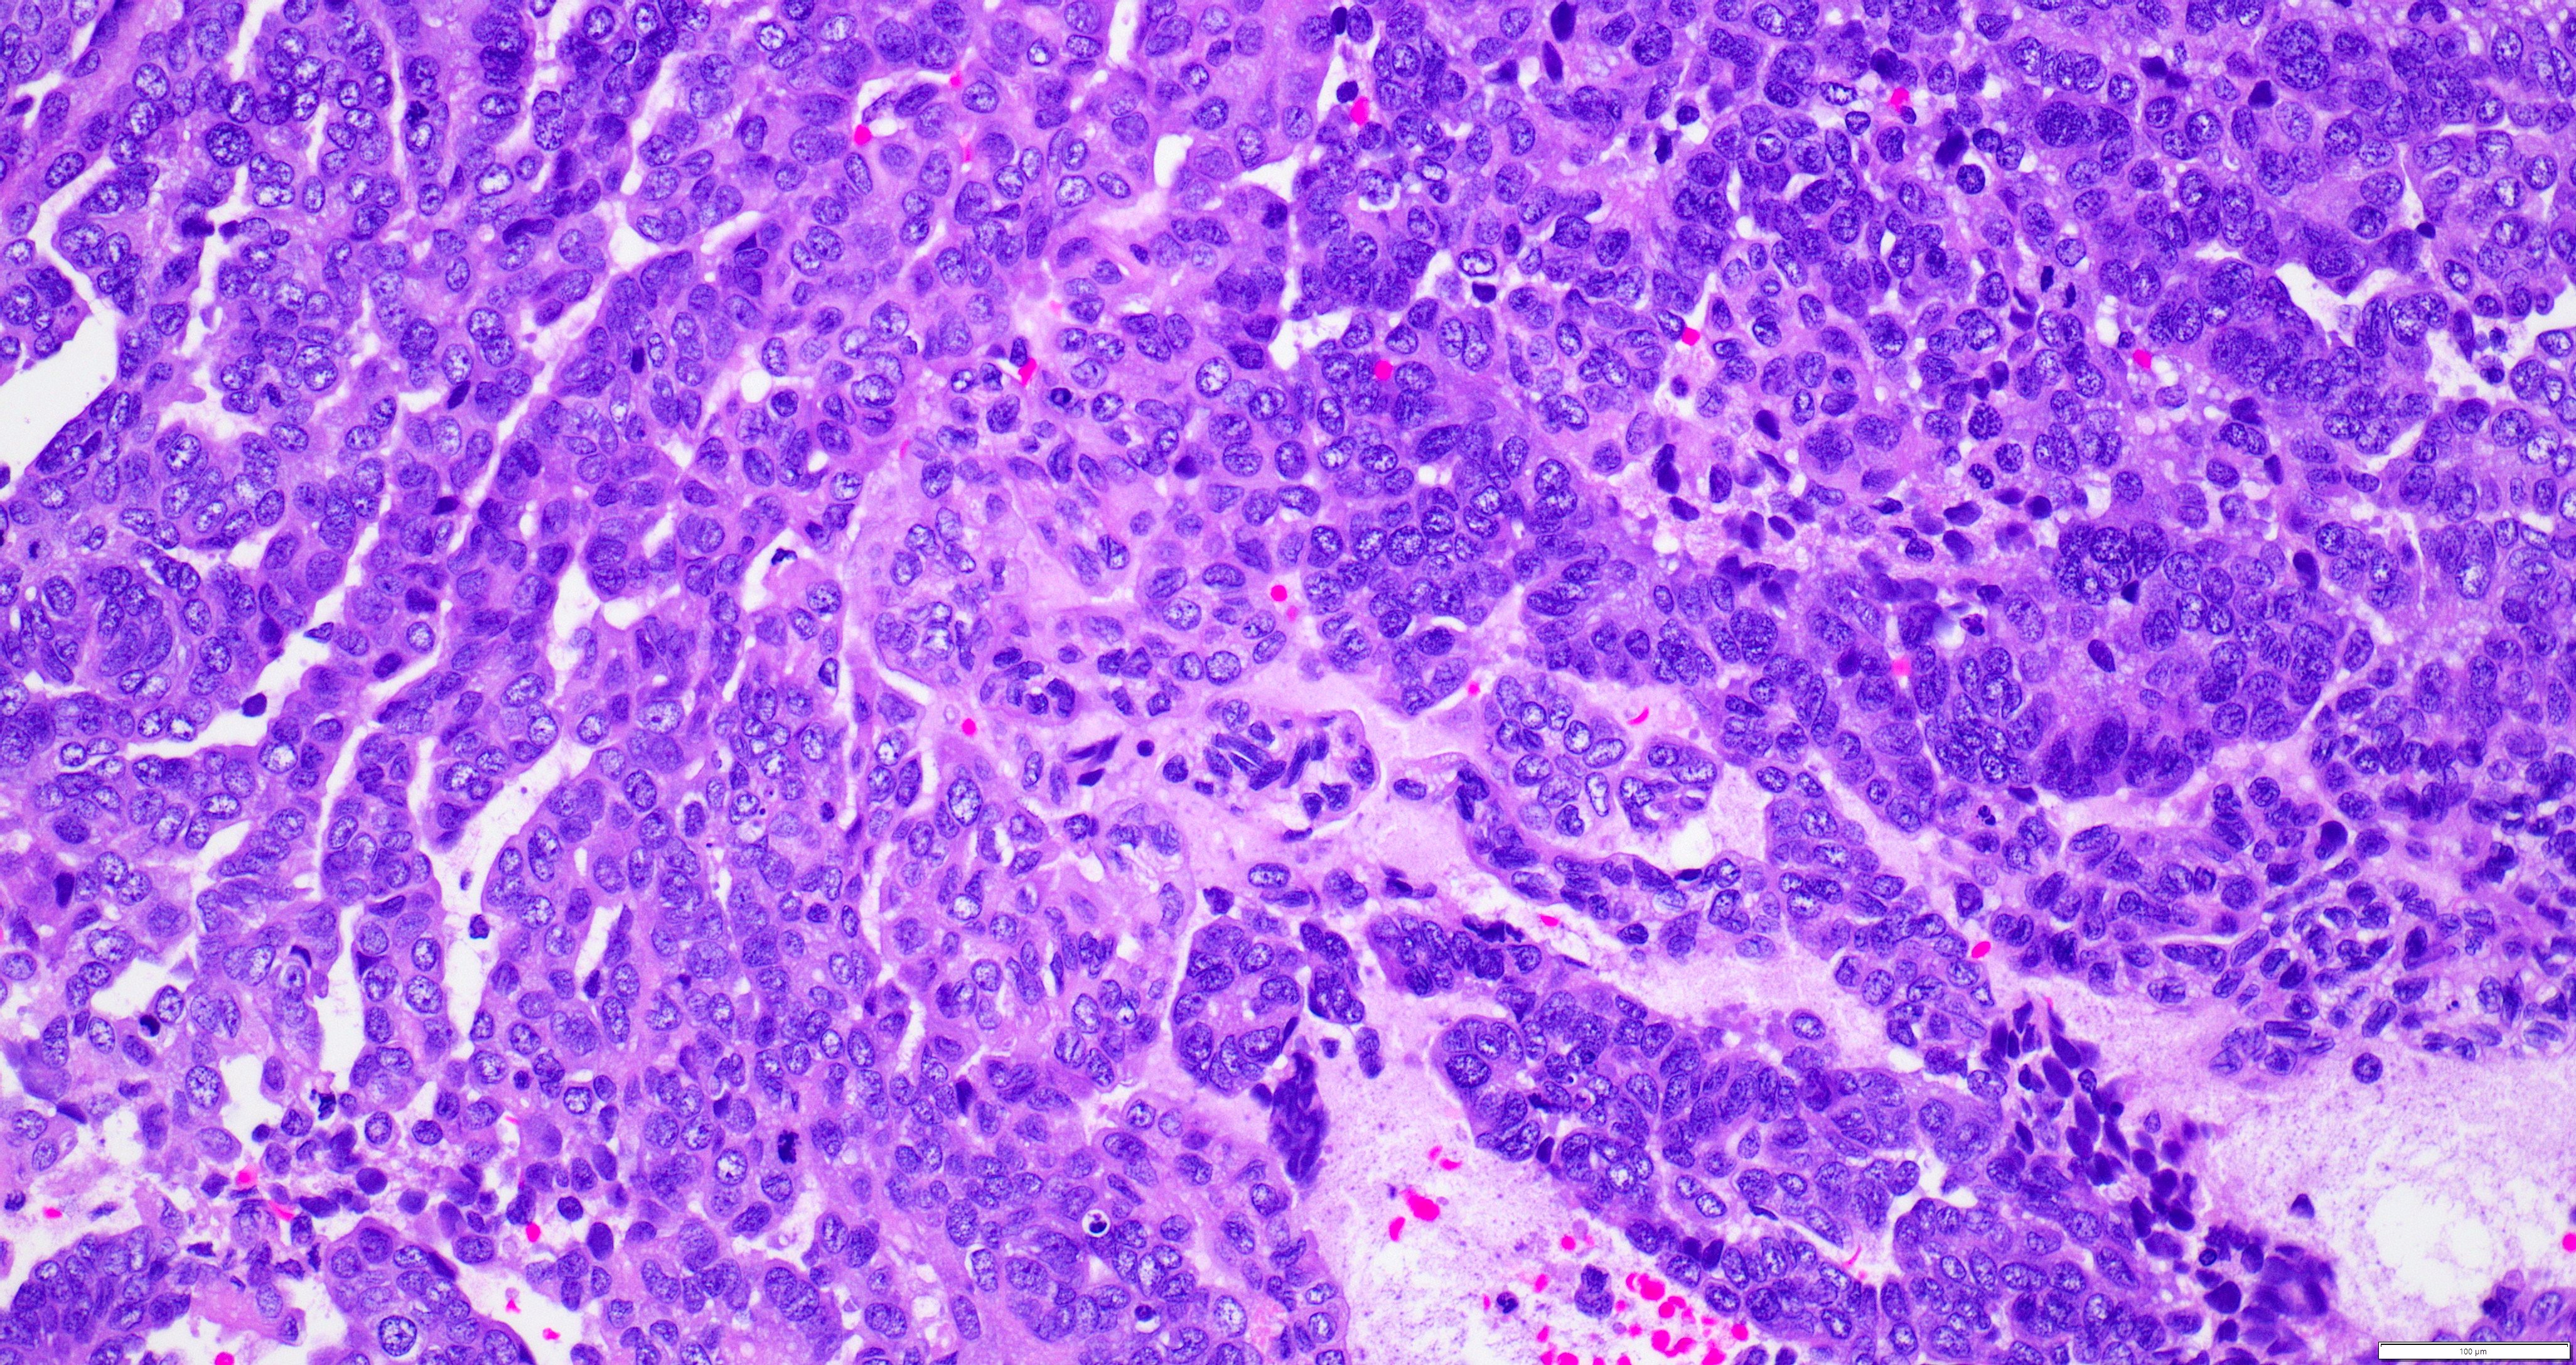

- Variety of histologic patterns that may be present within the same tumor

- Most frequently small tubules with ductal / glandular growth

- Papillary, solid growth, trabecular, retiform, sex cord-like, sieve-like, glomeruloid and spindle cell areas have all been described

- Luminal eosinophilic secretions are characteristic but not always identified

- Tumor cells can be flattened, cuboidal or columnar with mild to moderate cytological atypia

- Clear cell features can be seen but are less common

- High grade cytological atypia is usually not a predominant feature

- Nuclei show vesicular chromatin and nuclear grooves

- Sarcomatoid transformation has been seen in rare instances

- Squamous, ciliated or mucinous differentiation (metaplasia) are not present and there are no associated mesonephric remnants (J Clin Med 2021;10:698)

Microscopic (histologic) images

Contributed by Daniel Graham, M.D., Adele Wong, M.B., B.Ch., B.A.O. and Lucy Ma, M.D.